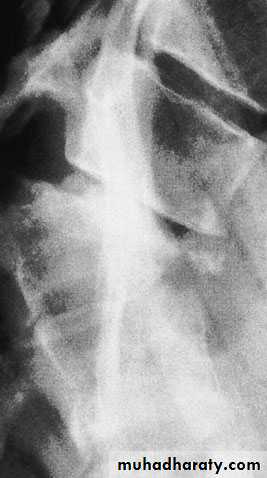

Flexion–compression injury

This is by far the most common vertebral fracture and is due to severe spinal flexion, though in osteoporotic occur with minimal trauma.

The posterior ligaments usually remain intact,

Pain may be quite severe but the fracture is usually stable.

Neurological injury is extremely rare.

Those with moderate wedging (loss of 20–40 per cent) of anterior vertebral height) and a stable injury can be allowed up after a week, wearing a thoracolumbar brace or a body cast applied with the back in extension.

If loss of anterior vertebral height is greater than 40

per cent, it is likely that the posterior ligaments have

been damaged by distraction and will be unable to

resist further collapse and deformity. If the patient is

neurologically intact, surgical correction and internal

fixation is the preferred treatment,